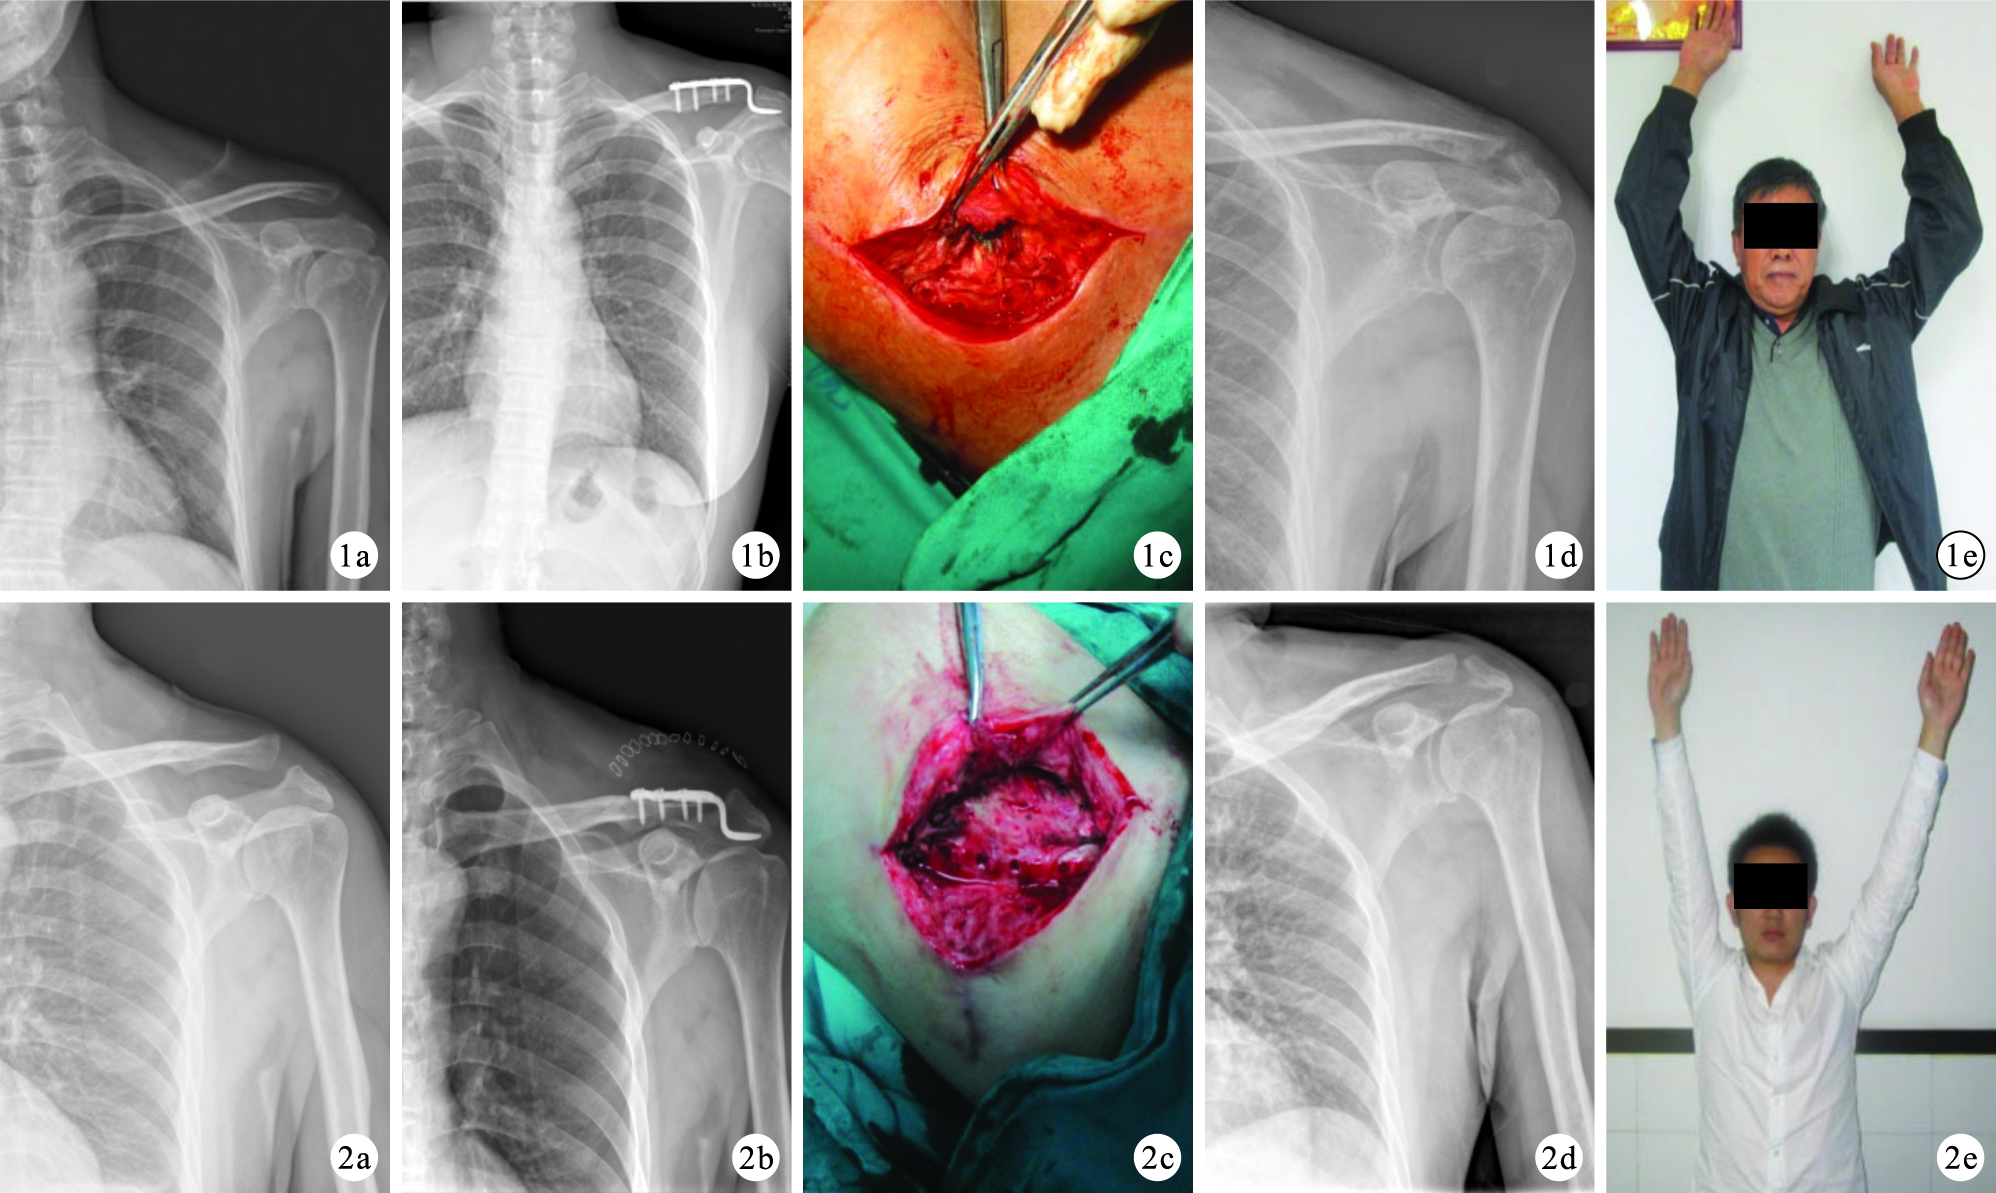

與B組比較,A組手術時間明顯延長,住院費用明顯降低,比較差異有統計學意義(P<0.05);兩組住院時間比較差異無統計學意義(t=1.046,P=0.316)。見表 1。兩組患者切口均Ⅰ期愈合,鉤鋼板均于術后3個月取出。兩組患者均獲隨訪,其中A組隨訪時間19~34個月,平均21.3個月;B組18~37個月,平均23.7個月。X線片復查示無肩峰下骨溶解等情況發生,兩組術前、術后1周及末次隨訪時的患肩喙鎖間隙比較,差異均無統計學意義(P>0.05)。隨訪期間,無肩鎖關節再脫位、排斥反應發生。末次隨訪時,兩組Constant-Murley評分、肩關節活動度及VAS評分比較,差異均無統計學意義(P>0.05)。見表 2。Constant-Murley評分評級:A組優11例,良2 例,一般2例;B組優13例,良2例,一般1例;兩組比較差異無統計學意義(Z=1.189,P=0.234)。見圖 1、2。